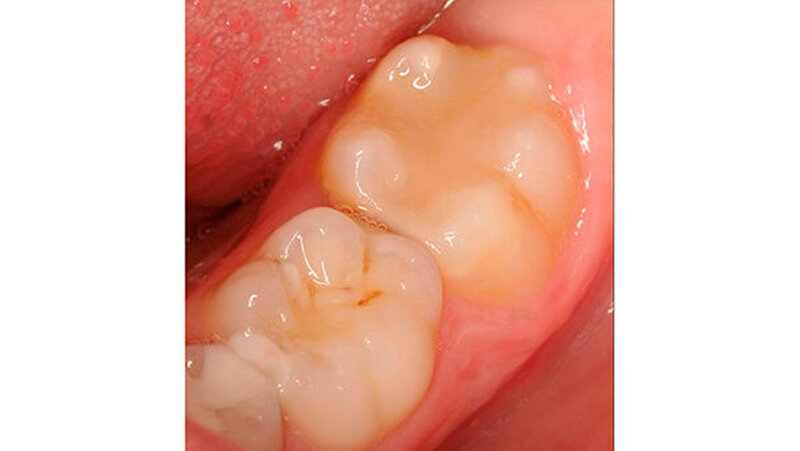

Bei einigen Patienten bestand allerdings auch schon im Milchgebiss eine Neigung zu Hypomineralisationen (Abbildung 3), klassifiziert wurden diese inzwischen als MDH (=deciduous molar hypomineralization) [Elfrink et al., 2012]. Inwiefern eine Hypomineralisation im Milchgebiss aber tatsächlich einen Indikator für eine MIH im bleibenden Gebiss darstellt, ist bisher nicht genauer zu beschreiben [Elfrink et al., 2012].